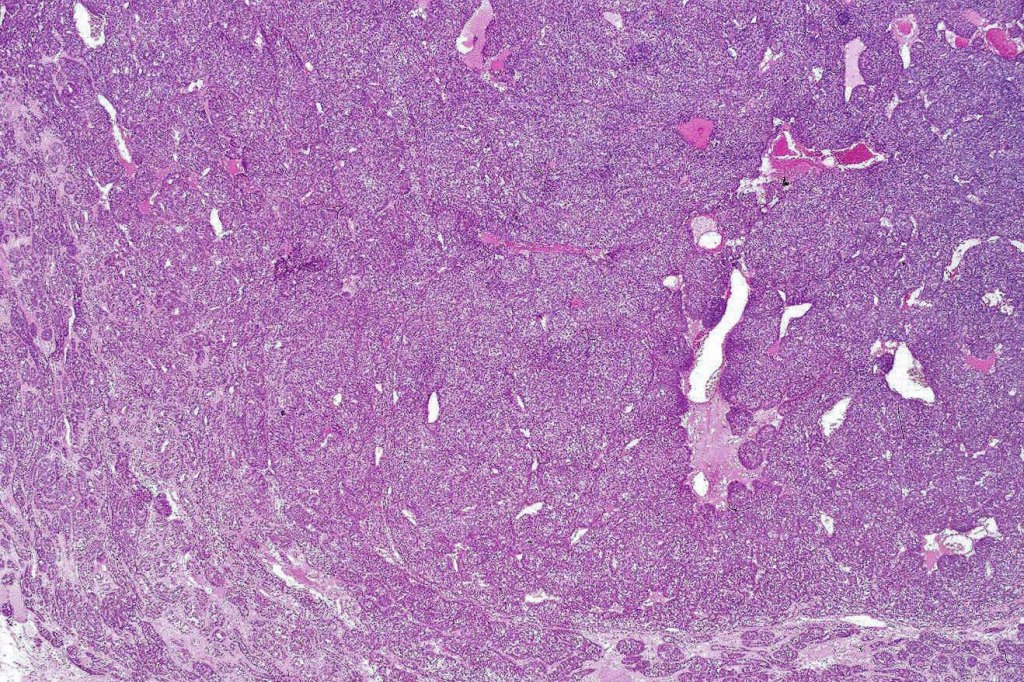

Histological features

•Pre-existent spiradenoma

•Malignant component shows loss of dual cell population, increased mitotic activity, atypical mitoses & necrosis

Classification

•1. Salivary gland type basal cell adenocarcinoma-like pattern, low grade (BCAC-LG)

•2. Salivary gland type basal cell adenocarcinoma-like pattern, high grade (BCAC-HG)

•3. Invasive adenocarcinoma, not otherwise specified (IAC-NOS)